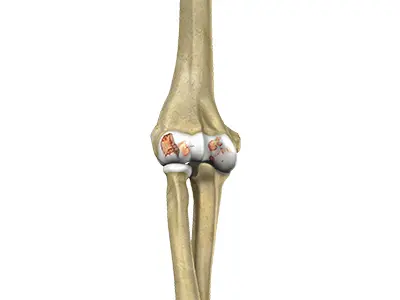

Distal Humerus Fractures of the Elbow

Injury in the distal humerus can cause impairment in the function of the elbow joint.

Radial Head Fractures of the Elbow

Radial head fractures are very common and occur in almost 20% of acute elbow injuries.